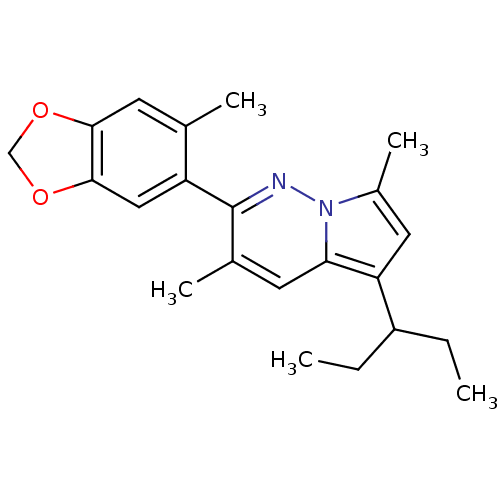

TargetCorticotropin-releasing factor receptor 1(Homo sapiens (Human))

Dupont Pharmaceuticals

Curated by ChEMBL

Dupont Pharmaceuticals

Curated by ChEMBL

Affinity DataEC50: 0.600nMAssay Description:Antagonist activity at human CRF1 receptor expressed in CHO-K1 cells assessed as CRF-stimulated cAMP accumulation by enzyme immunoassayMore data for this Ligand-Target Pair